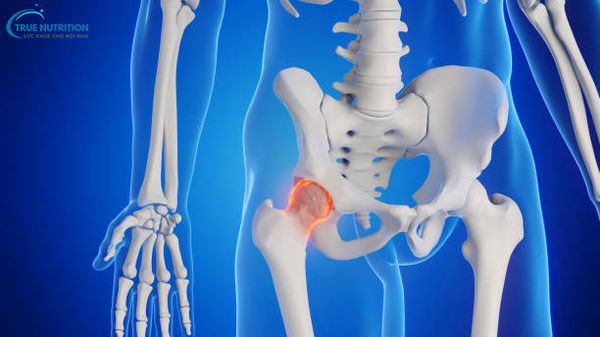

Định nghĩa: Chỏm xương đùi là phần đầu trên của xương đùi, có hình dạng 2/3 khối cầu, hướng lên trên và vào trong, tham gia cấu tạo nên khớp háng.

Chức năng: Chỏm xương đùi kết hợp với ổ cối của xương chậu tạo thành khớp háng, cho phép các chuyển động linh hoạt của chân.

Hoại tử chỏm xương đùi, hay hoại tử vô khuẩn chỏm xương đùi, là tình trạng thiếu máu nuôi dưỡng dẫn đến hoại tử tổ chức xương và sụn tại vùng chỏm xương đùi.